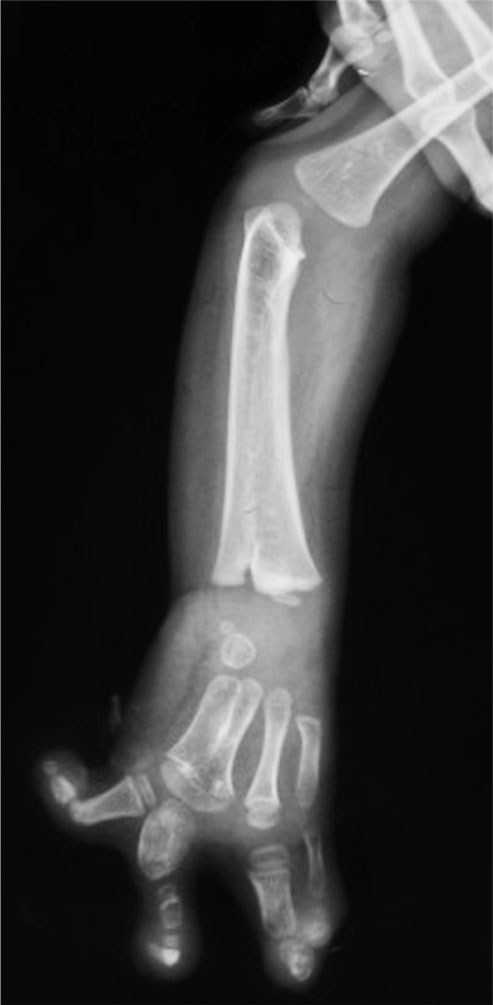

图1-2-36 右手内生软骨瘤病

(2)内生软骨瘤病(图1-2-36)。